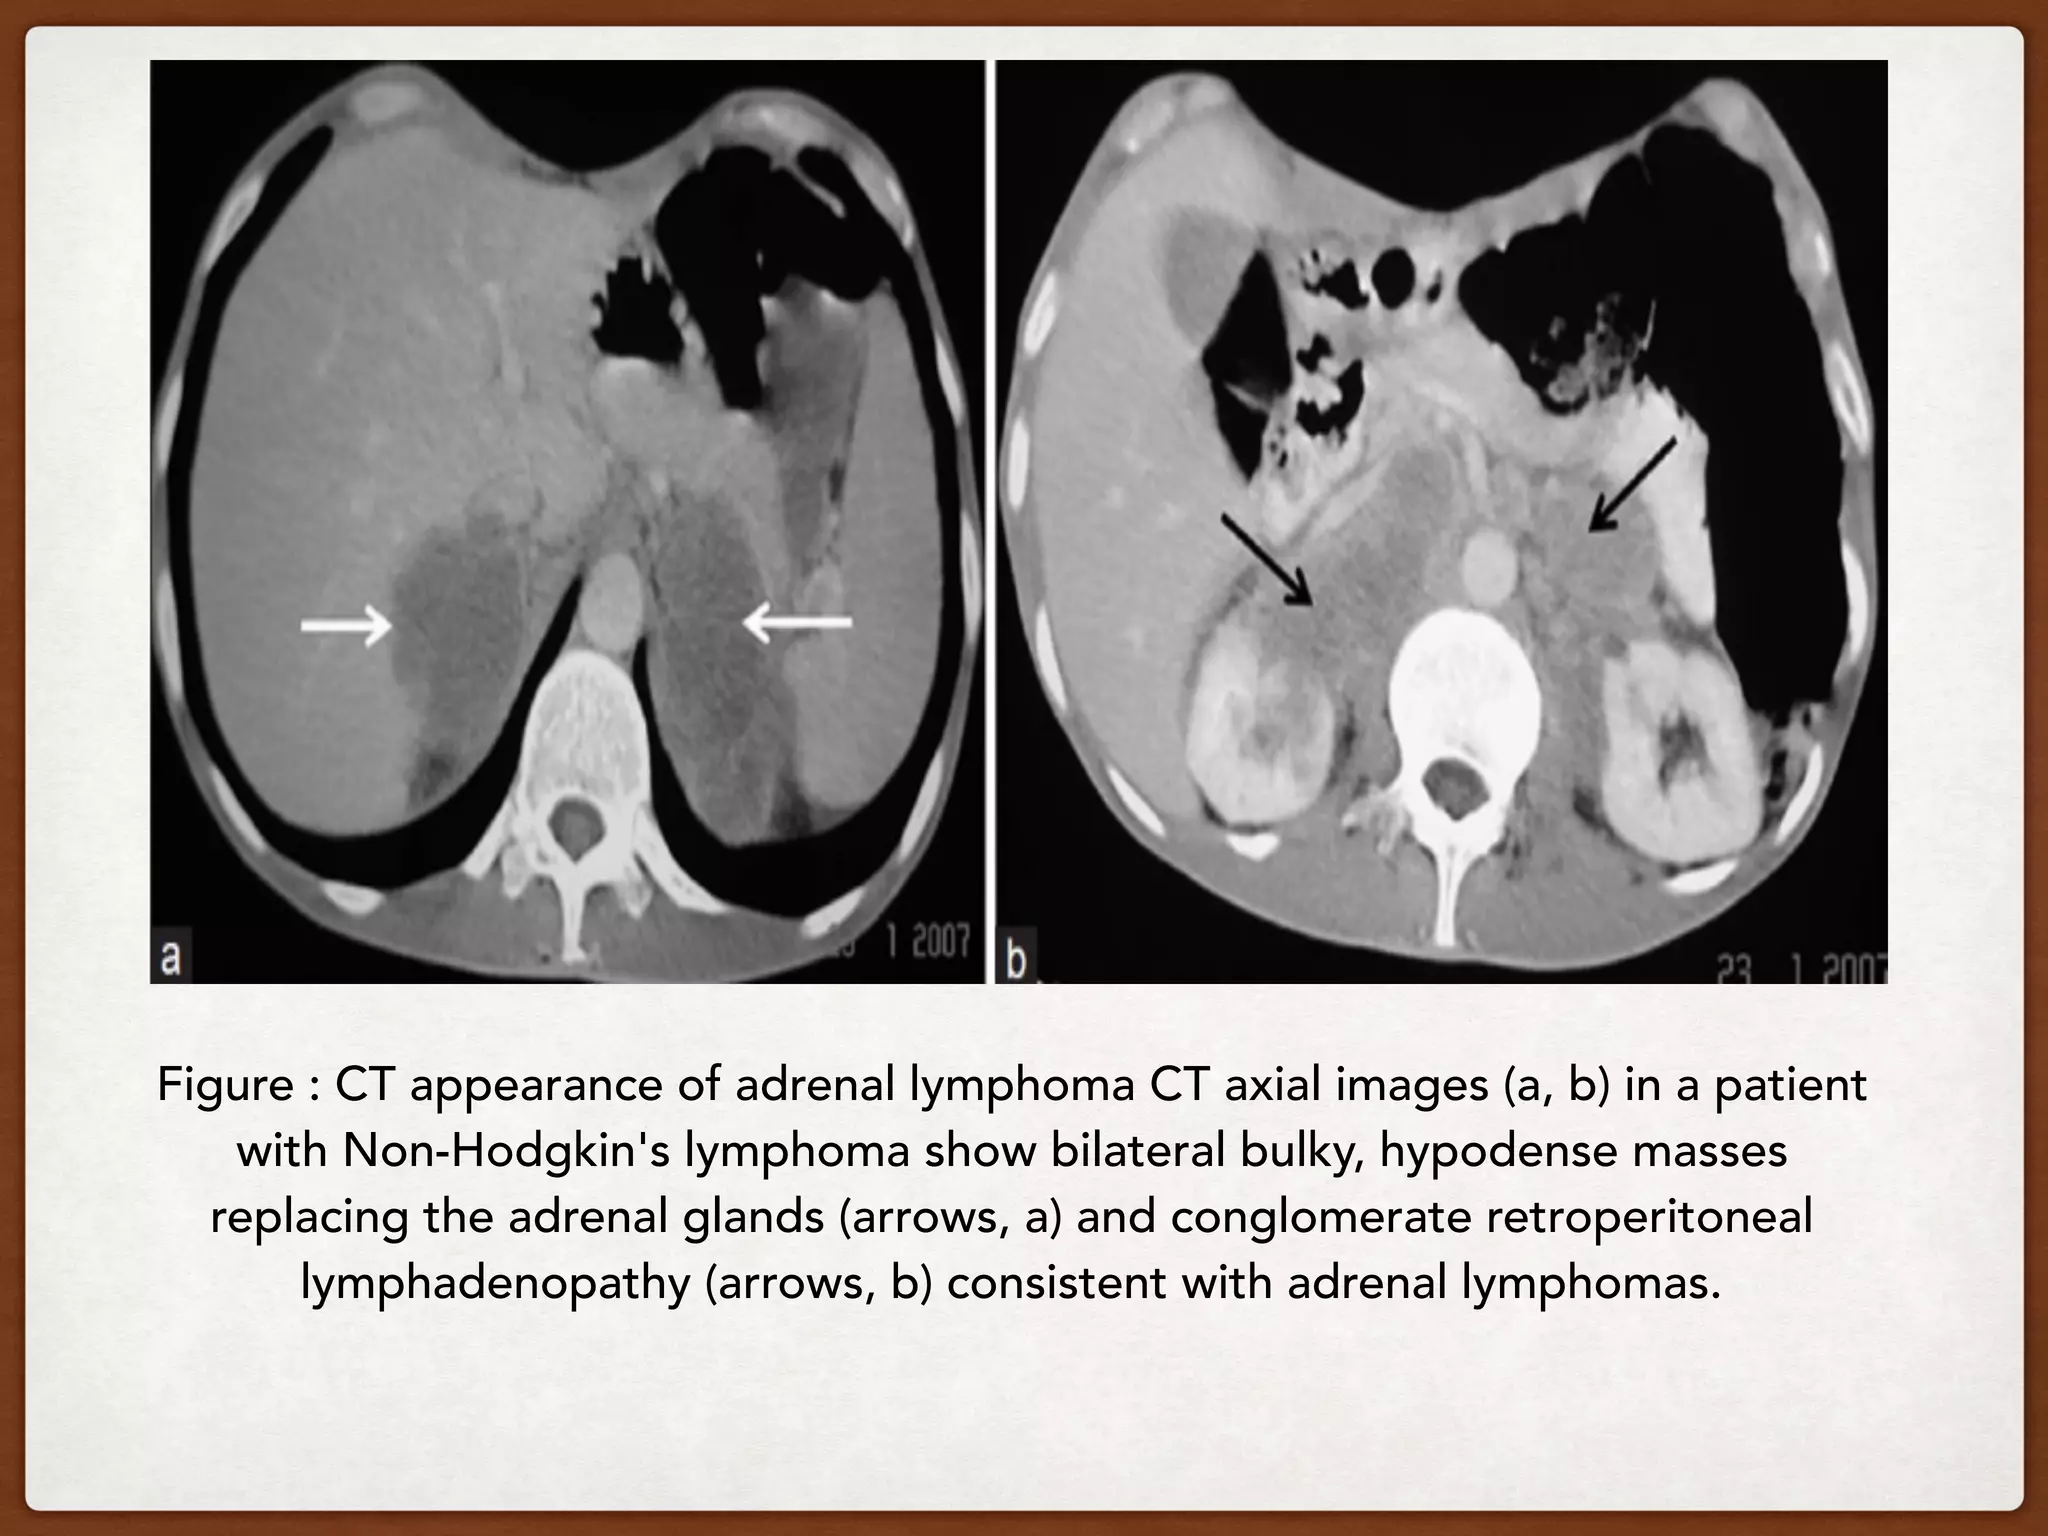

Figure : CT appearance of adrenal lymphoma CT axial images (a, b) in a patient

with Non-Hodgkin's lymphoma show bilateral bulky, hypodense masses

replacing the adrenal glands (arrows, a) and conglomerate retroperitoneal

lymphadenopathy (arrows, b) consistent with adrenal lymphomas.